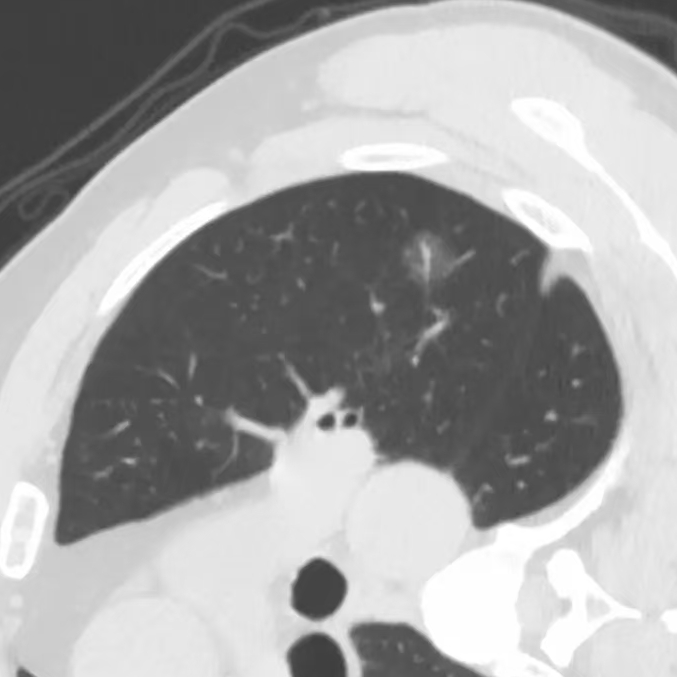

健康直通车: 健康是生命的宝贵财富,也是幸福生活的基石。为了更好地服务广大百姓,传播健康知识,葫芦岛市第二人民医院推出“健康直通车”专题栏目,将专业的医学知识以通俗易懂的方式传递给每一位市民,掌握科学的疾病预防方法,共同构筑健康中国的坚实基石。 什么是肺结节 肺结节是指肺内直径小于或等于3cm的类圆形或不规则形病灶,影像学表现为密度增高的阴影。大于3cm的称肿块。肺结节依其密度不同可分为实性结节、部分实性结节、磨玻璃结节,其中部分实性结节的恶性可能性最大,磨玻璃结节次之,实性结节尤其是小的实性结节结节最可能是良性的。 肺结节的常见病因 1、良性(约90%) 🔸 感染:结核、真菌、细菌性肺炎后遗留的瘢痕; 🔸 非感染:错构瘤(良性肿瘤)、炎性假瘤、血管瘤等。 2、恶性(约10%) 🔸原发性肺癌(如腺癌、鳞癌); 🔸转移性肿瘤(其他器官癌症转移至肺)。 如何根据影像判断肺结节性质 1、依据结节大小判断 🔸小于0.5cm的肺结节绝大多数都是良性的,属于微小结节。即使部分小于0.5cm肺结节是恶性的,但是适当的观察不影响预后。每年复查一次胸部CT就可以。 🔸大于0.5cm持续存在的纯磨玻璃结节,观察6个月,若持续存在,不管有无进展均多数是恶性的,视患者意愿,手术可以立即做也可观察至进展再做,不影响预后。 🔸大于0.8cm的部分实性结节恶性可能性非常大,应积极评估结节边缘毛刺、分叶、胸膜凹陷等征象。 🔸若实性部分大于0.5cm,恶性率显著提高。若在3~6个月随访期间实性部分增大或者总体部分增大,都可以考虑手术切除。而即使小于0.8cm的部分实性结节也需3个月就复查对比。 2、依据肺结节形态 如CT上提示病灶形态不规则、毛刺、分叶、胸膜凹陷、空泡征、血管集束征等,符合恶性肿瘤的征象。 🔸结节与正常肺组织之间界限非常清楚的恶性可能性大。 🔸结节密度不均呈混杂密度或均匀较大纯磨玻璃结节也基本是恶性的。 🔸有胸膜牵拉(不管是肺表面的脏层胸膜还是叶间裂部位的胸膜)的恶性可能性大。 🔸结节有浅分叶、细毛刺,密度较高而与周围肺组织边界不清的恶性可能性大。 🔸磨玻璃或混合磨玻璃结节存在小空洞的恶性可能性大。 🔸影像上似慢性炎表现,而没有炎症相关的其他异常,特别当所谓炎症区域内部或一侧与正常肺组织之间界限非常清楚的基本上是恶性的。 3、从结节发展情况来看 所有随访中增大进展的都需要考虑恶性可能,不进展而持续存在的纯磨玻璃结节也需考虑恶性。 葫芦岛市第二人民医院肺结节诊治中心孙振教授深耕肺结节领域四十余载,凭借对临床实践的执着钻研与深厚积淀,在肺结节精准诊断及鉴别诊断领域形成独到见解。他系统总结海量临床病例,创新性提炼出一套科学化、规范化的肺结节全周期诊疗体系,尤其在早期微小结节的影像特征识别、良恶性风险分层等方面积累了丰富经验,为众多患者提供了精准、高效的诊疗方案。 人民医院·人民名医 孙振 主任医师 三级教授 ·葫芦岛市第二人民医院胸外科主任、肺结节诊治中心主任 ·中国医科大学客座教授 ·原央企总医院著名胸外科专家 ·辽宁省医学会胸外科委员 ·辽宁省抗癌协会肺癌专业委员会委员 ·辽宁省细胞生物学学会食管癌专业委员会理事 ·主持多项科研成果获科技成果奖、科技进步奖、国家专科奖项 医学成就 从事胸外科临床工作近40年,担任胸外科首席专家及科室主任20余年,是我省胸外科领军人物,推动肺癌、食管癌等胸部肿瘤外科的规范化诊疗,在央企总医院牵头成立了肺结节诊疗中心,率先开展CT引导下肺内小结节定位切除,既确切完整切除肺内小结节,又降低肺功能损害。 专业特色 擅长肺癌、食管癌的外科手术和综合治疗,在各类高难度胸外伤手术治疗、胸腔镜微创手术、胸腺瘤手术及复杂并发症处理方面具有高深造诣,尤其擅长肺癌早期诊断,胸部小结节CT早期肺癌的鉴别等。完成各类高难度胸外科手术5000余例,其中微创手术占比达90%,治愈率达98%,多项业务填补省内空白。 开展的高难手术 胸腔镜肺部结节微创手术、肺癌根治术、食管癌根治术、各种纵隔肿瘤切除术、胸骨后甲状腺手术及胸部复合性外伤的抢救手术等。